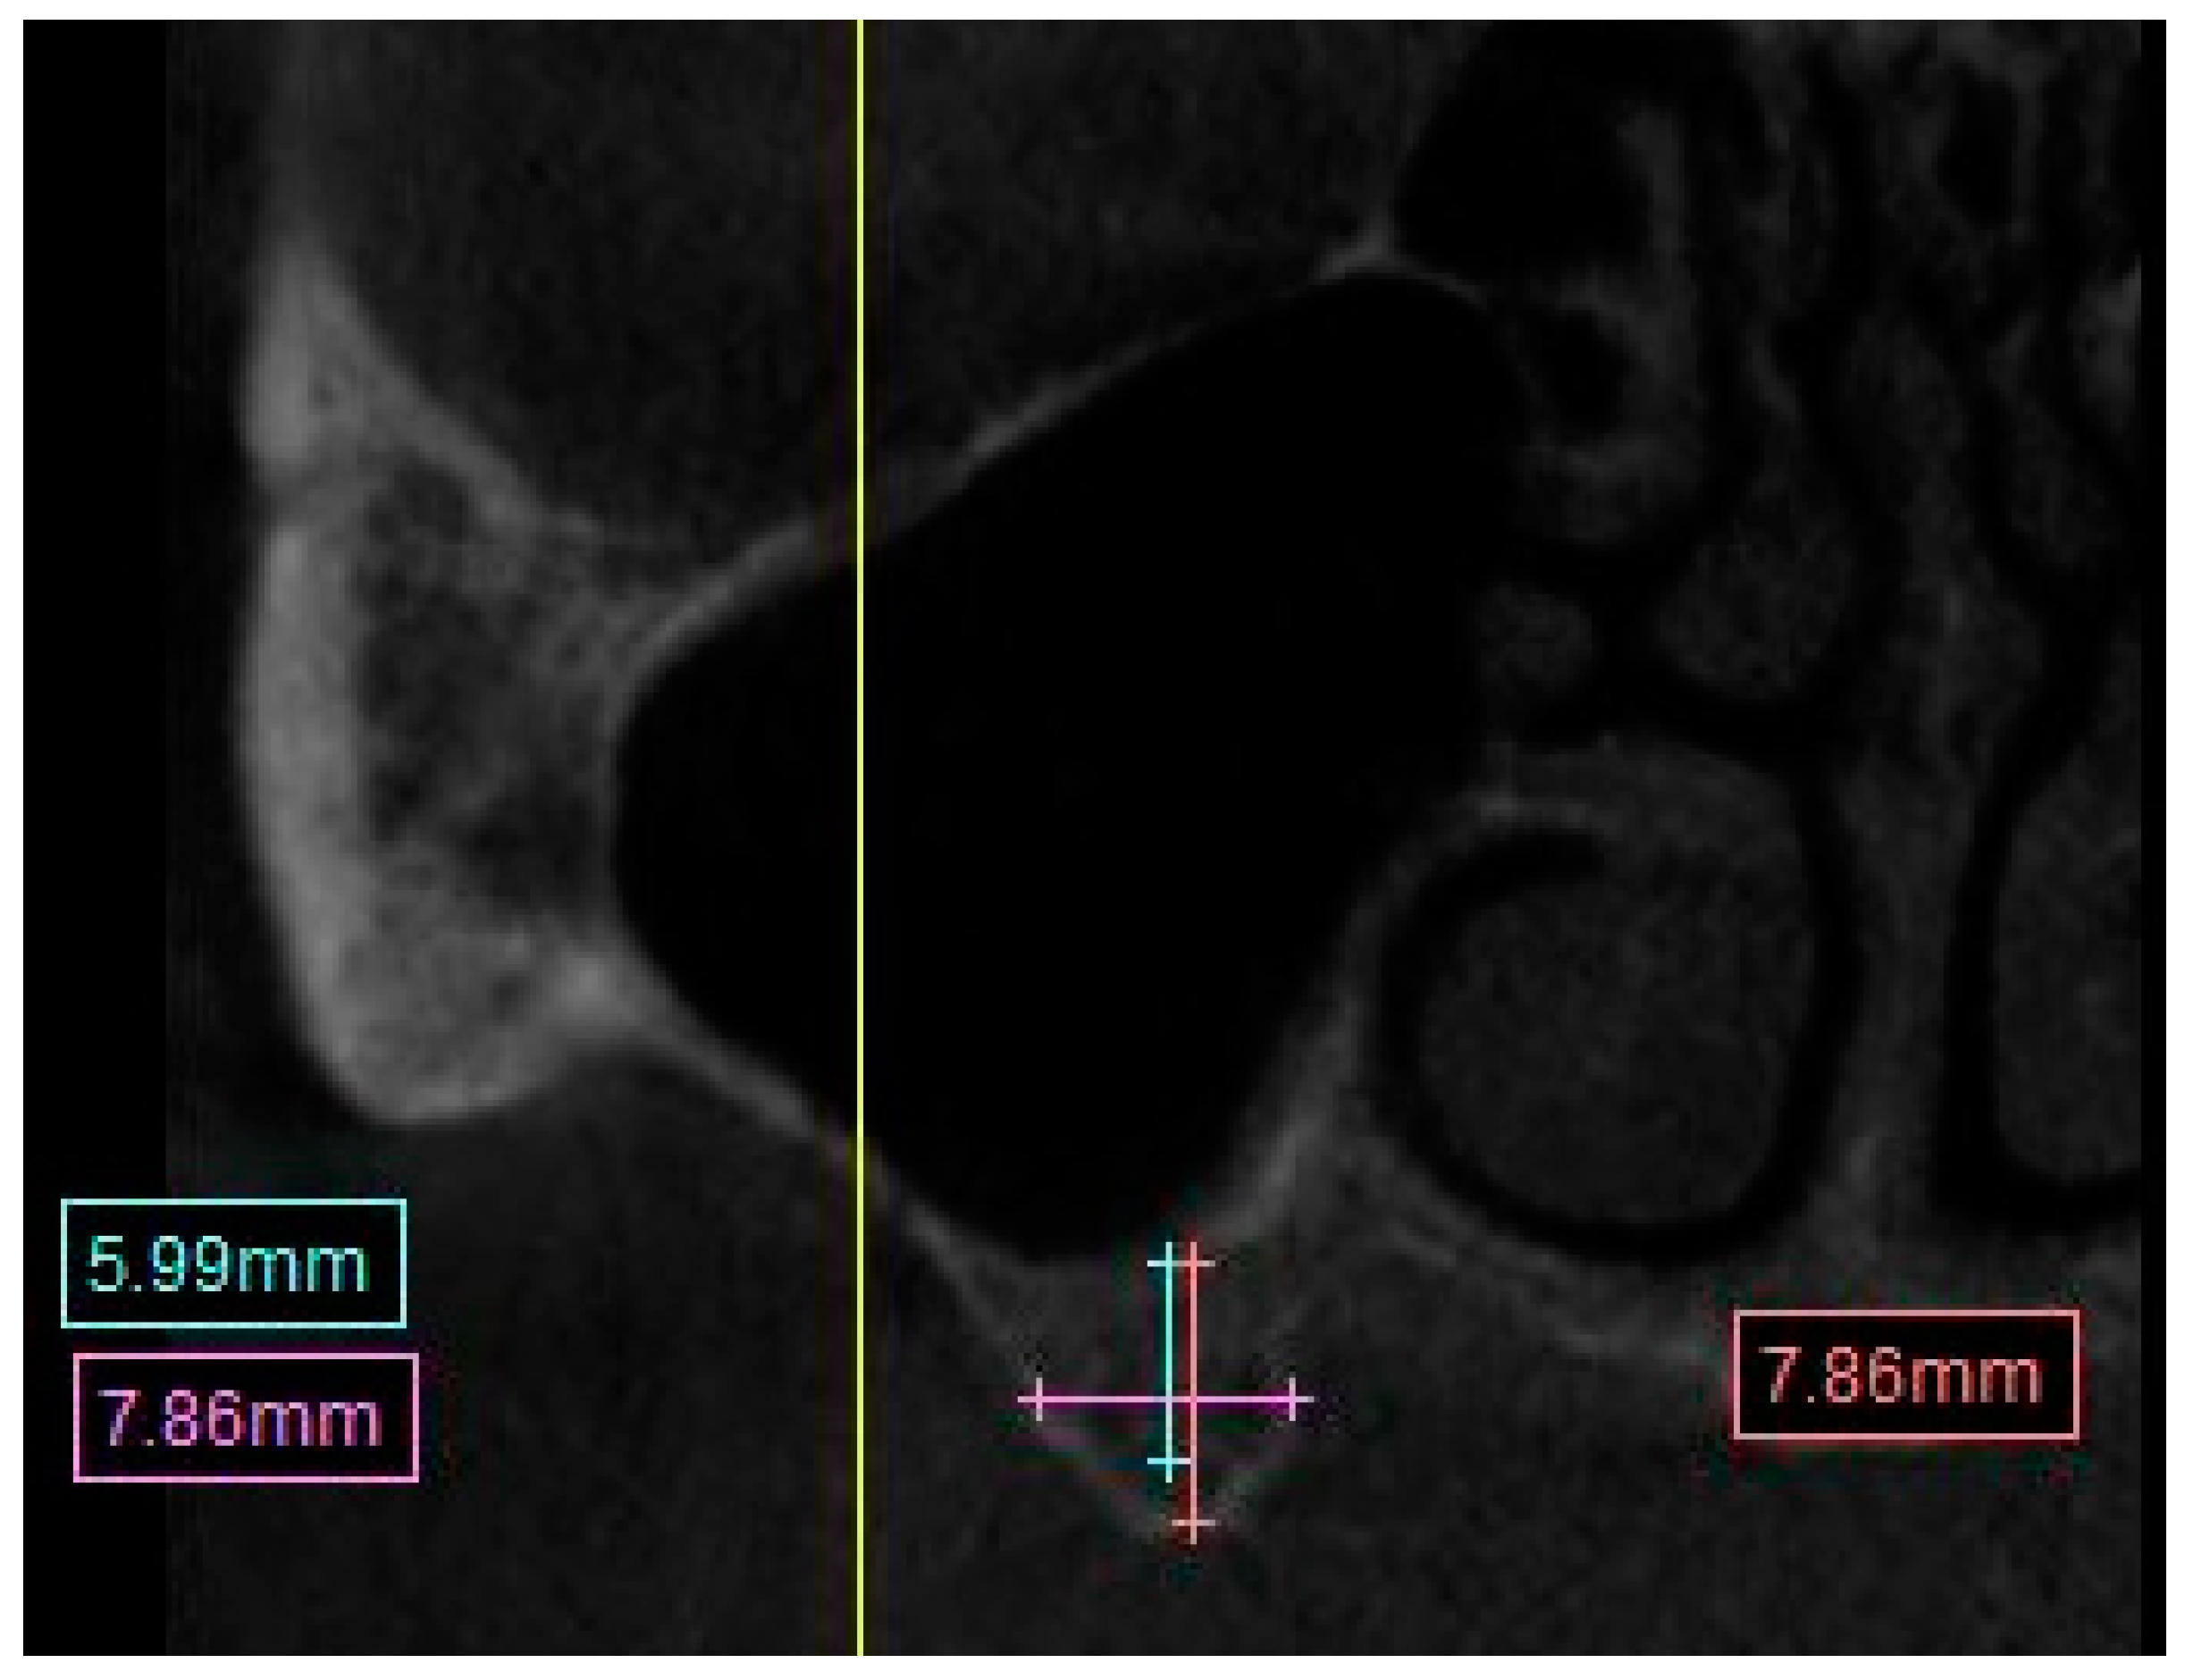

• Distance from crest of bone to the mental foramen. (Figure 5)

The measurement was taken from the most mesial slice onto which the mental foramen opens inside the oral cavity, the measurement was taken from the most superior boarder of the mental foramen to the edge of the crest in a straight line.

Figure 5. CBCT Image showing the measurement calculation for the distance from mandibular ridge to the superior boarder of the mental foramen.